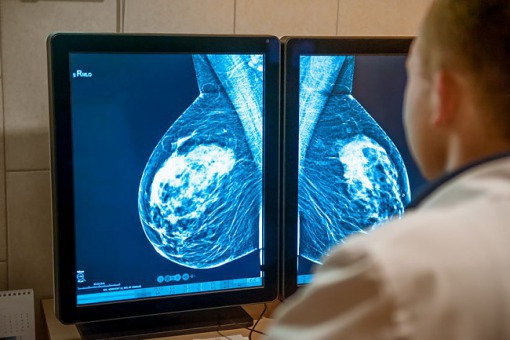

Pomimo znaczących postępów w leczeniu raka piersi we wcześniejszych stadiach, nadal wyzwanie stanowi terapia rozsianego raka piersi, a w szczególności dotyczy to dalszych linii leczenia. Dla tej grupy chorych możliwości kontynuacji leczenia i wydłużenie życia są ograniczone, zwłaszcza u pacjentów z przerzutami. U około 15-20 proc. wszystkich chorych na raka piersi występują guzy HER2+. Szacuje się, że w Europie to około 79 560 – 106 200 osób. HER 2-dodatni rak piersi jest bardziej agresywny, rośnie i rozprzestrzenia się znacznie szybciej niż inne nowotwory piersi.

Rak piersi jest najczęściej występującym nowotworem zarówno w Europie, jak i na świecie, 70 proc. zdiagnozowanych to osoby w wieku 55+. Zazwyczaj u 30 proc. pacjentek, u których początkowo zdiagnozowano raka piersi we wczesnym stadium, rozwinie się choroba przerzutowa. Przerzuty są odpowiedzialne za ponad 90 proc. zgonów związanych z nowotworami. 5-letni względny wskaźnik przeżycia chorych z przerzutowym rakiem piersi wynosi 27 proc. Do 50 proc. pacjentów z rakiem piersi z przerzutami HER2+ rozwinie przerzuty do mózgu. Pacjenci ci będą mieli większe prawdopodobieństwo obniżonej jakości życia związanej ze zdrowiem (HR-QoL) w porównaniu z pacjentami bez takich przerzutów.